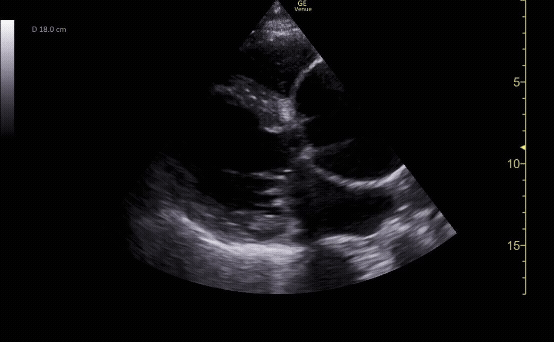

Parasternal short view showing the left ventricle and right ventricle at the level of the papillary muscles.

c/o Kyle Ackerman, MD